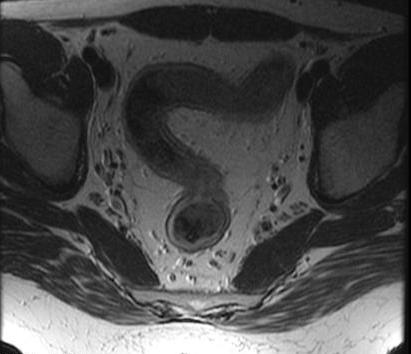

Aspect

TDM d'une colite ulceree ( ulceretive colitis ) .

IRM du colite ulcere

| |

Aspect IRM d'une colite

ulceree est image de epaissisement de couche mediane

de la paroi du colon . Generalement la couche

mediane de la paroi du colon est a moindre de 3mm ,

de 3-4mm est restricle " gray zone " et de plus >

4mm est pathologique . |

|

Et le plus souvent est la

perdre de haustral du colon et la colon sigmoide est

en forme tubule |